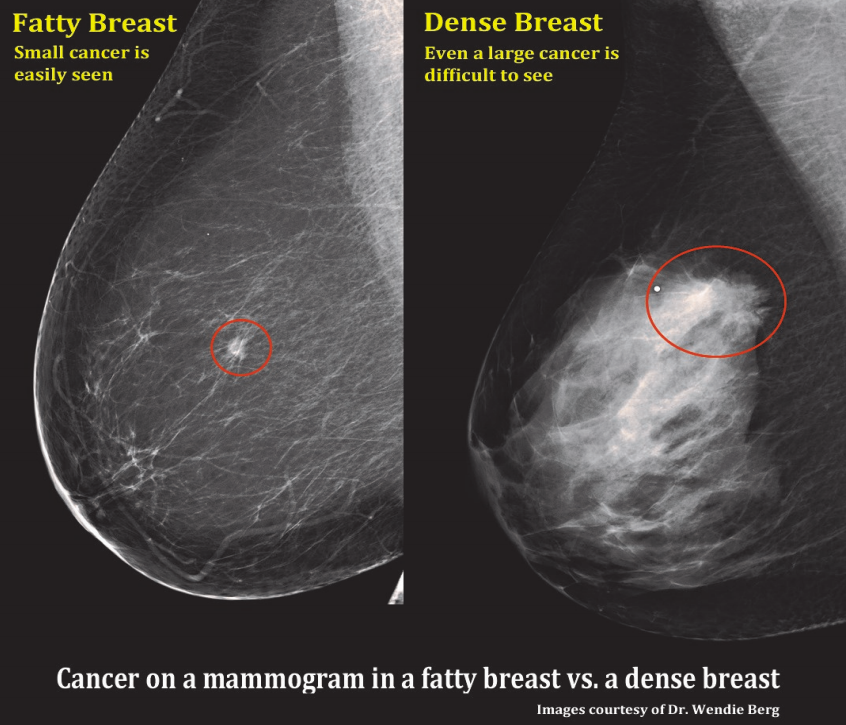

In every mammogram report, breast tissue is categorized from A to D:

A cancer shows up as white on mammogram, as does dense breast tissue. A picture is worth a thousand words—in this case, demonstrating how much harder it is to see a breast cancer in dense breast tissue!